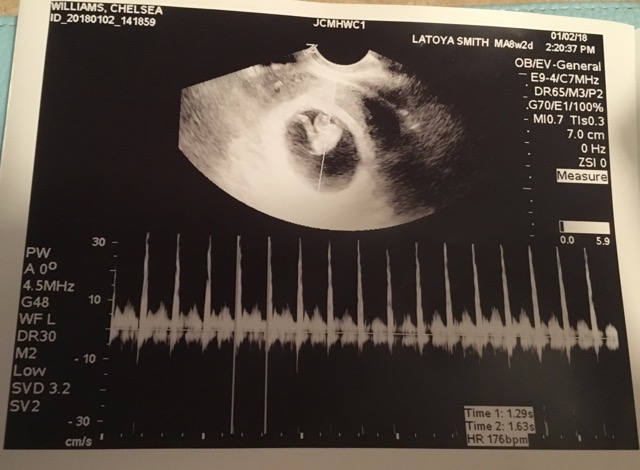

We had our first scan at 8 weeks & 2 days. It was internal. I’m now 13 weeks & 1 day. We won’t have another scan done until around 20 weeks to find out the gender. I’m just so excited to find out because we’re waiting to plan & but stuff until we know.

Here’s my 8 week scan. Any gender guesses?